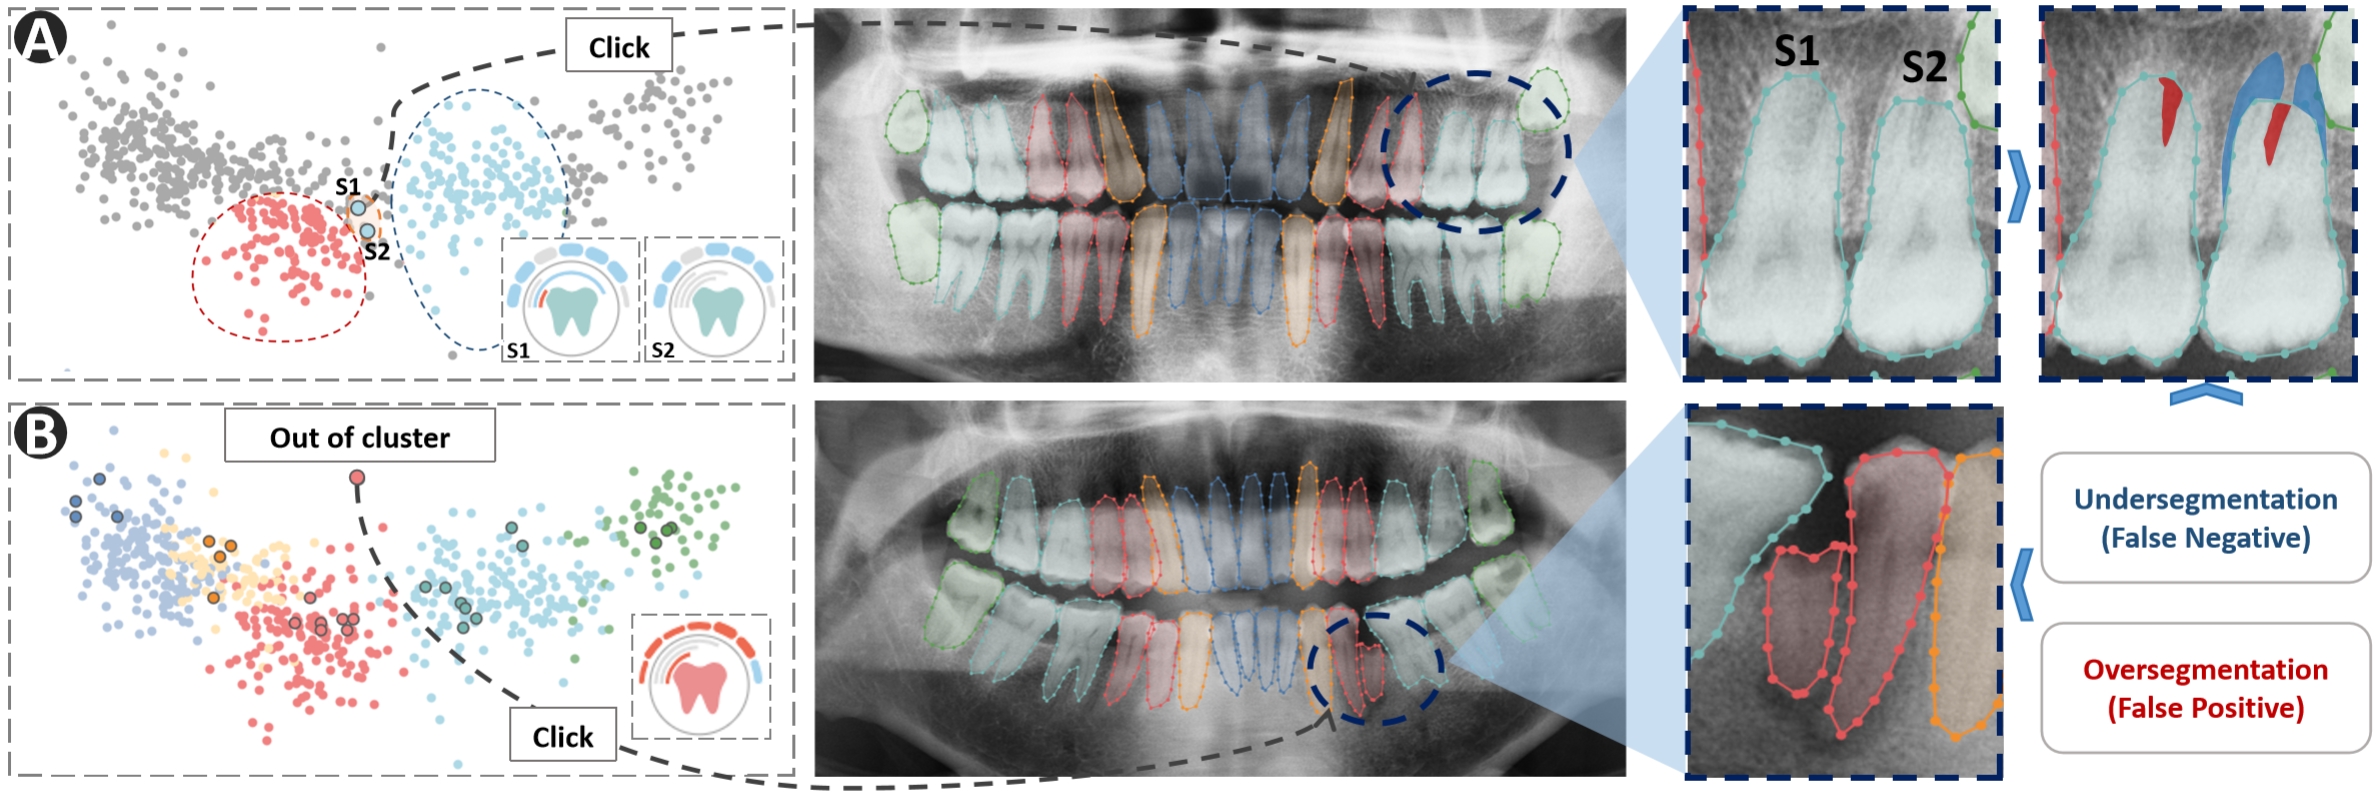

We invited E1 to utilize VisTooth for detailed human-machine collaborative segmentation of teeth on 10 panoramic X-ray images, and asked him to follow the system’s visual cues during the process. In the process of the segmentation task, all corrections and feedback were recorded. Initially, the segmentation model achieved an accuracy of 74.91%, which was unsatisfactory. Thus E1 would like to use the system to inspect and refine the model outputs. Immediately, E1 identified some abnormal outliers from the scatter plot view(Figure 4). He first clicked on an outlier to locate the tooth represented by it, concurrently the similarity view was updated to display detailed glyph and show samples similar in height to the selected sample. Upon observation, E1 found that one case of the outlier might be attributed to incomplete segmentation, leading to a significant separation between the mask and the regular distribution of that category. Figure 4(A) illustrates how E1 corrected examples of teeth S1 and S2 by examining the morphology in the similarity view. Typically, the second molars have two roots, but due to the proximity of the pixel values between the root and the gingival tissue in the S1 and S2 regions, the model struggles to accurately differentiate tooth structure from other tissues. And the glyph in similarity view suggests that despite its mask features deviating from the second molar and resembling the first molar, its coordinate and angular features closely match those of the 2nd molars as predicted by the model. Subsequently, E1 attempted to adjust the contrast of the panoramic radiograph using the toolbar to enhance the differentiation between the target teeth and other structures, then manually adjusted the contour points to restore precise positioning. Furthermore, E1 also found that some cases characterized by individual differences could lead to outliers, as depicted in Figure 4(B). Here, the patient exhibited incomplete tooth structures, significantly deviating from the training samples. Such situations bears the potential for erroneous segmentation, requiring manual assessment. E1 highly praised the glyph design, ”Utilizing feature indicators as visual cues to help us detect segmentation anomalies for further manual correction is beneficial in the absence of ground truth for the newly loaded panoramic image.”